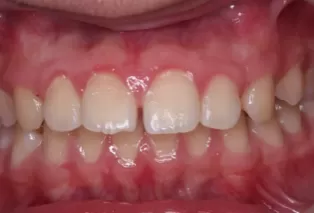

Photos intra-orales